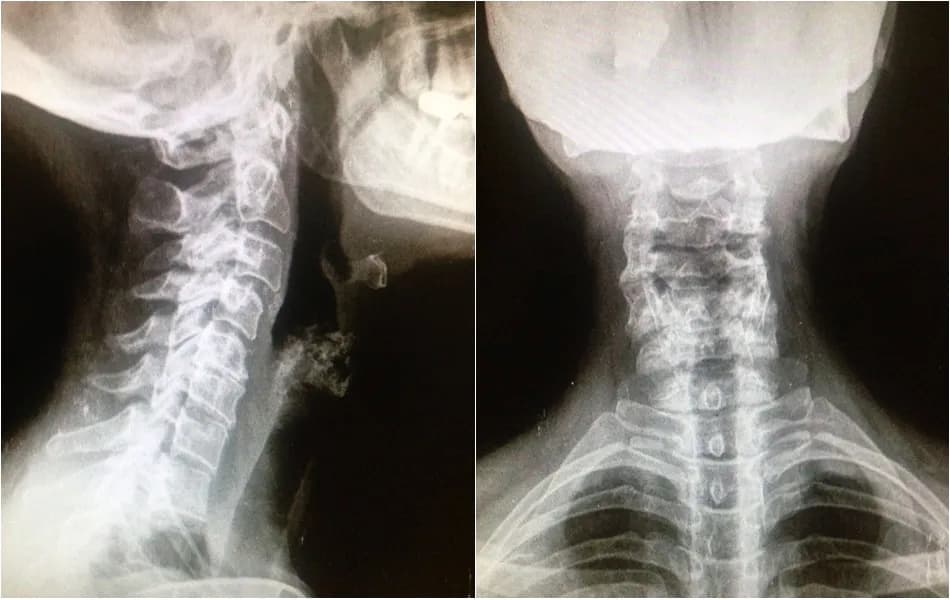

Conoce los síntomas de artrosis cervical grave, como dolor y debilidad, y aprende a identificarlos para buscar la atención médica adecuada a tiempo.